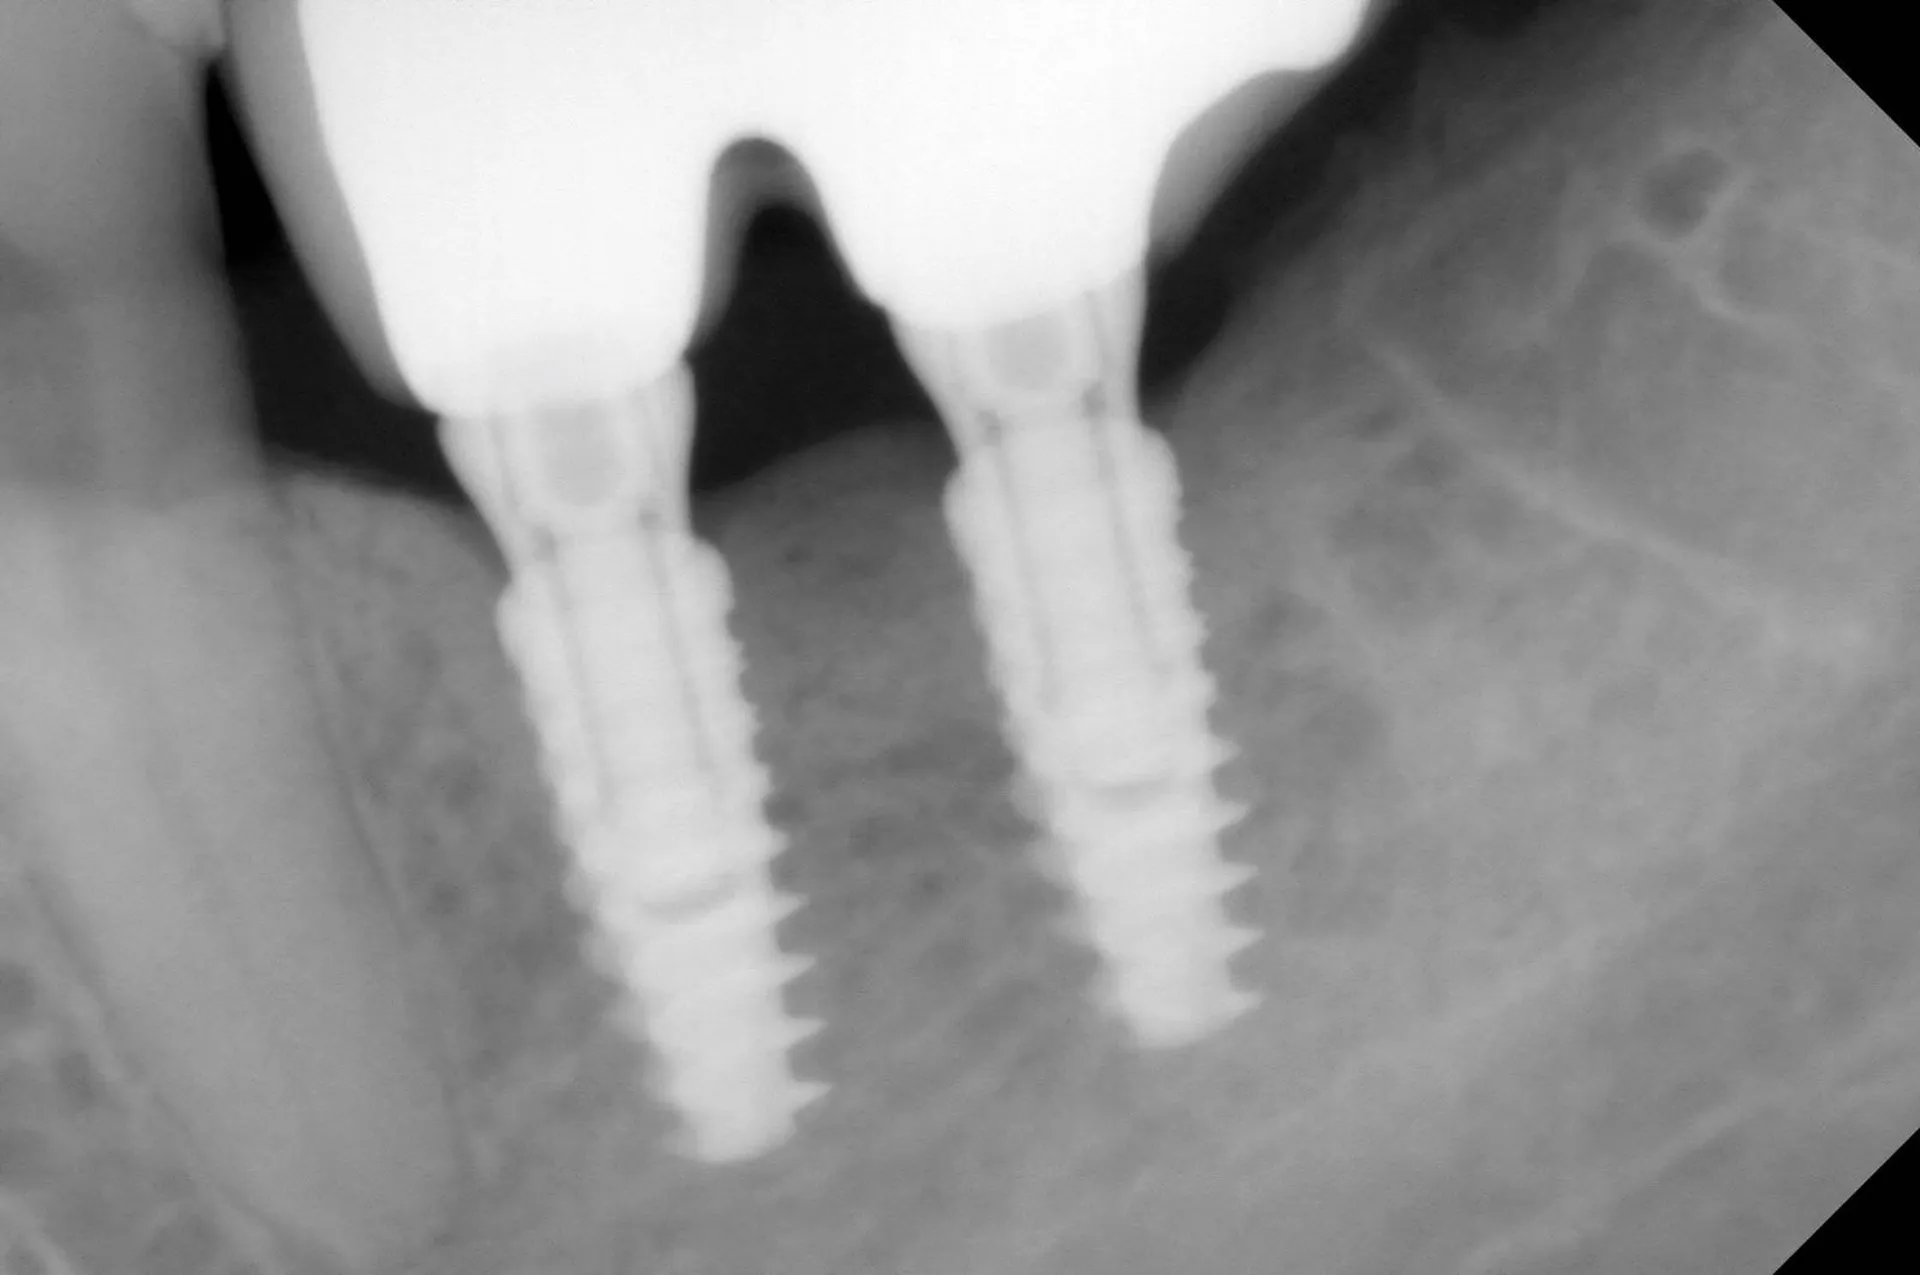

L'implant dentaire est actuellement la solution idéale pour remplacer les dents absentes ou fracturées.

Cette technique est devenu incontournable pour remplacer une dent absente. C'est la technique de choix qui permet de remplacer des dents infectées ou remplacer des dents fracturées.